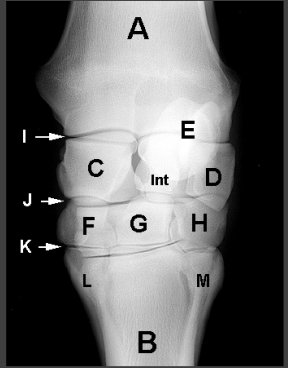

Carpus:

A - Radius

I - Antebrachiocarpal joint

E - Accessory carpal bone

J - Middle carpal joint

G - Third carpal bone

K - Carpometacarpal joint

B - Third metacarpal bone

L - Second metacarpal bone

M - Fourth metacarpal bone